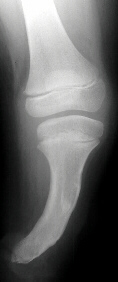

FOLLOW-UP: At 9 years of age the patient was noted to have an increased flexion contracture about the knee with radiographs demonstrating a recurrent valgus deformity. She subsequently underwent a repeat tibial derotational osteotomy with correction of the valgus deformity. Her postoperative course was uncomplicated. Currently she is 17 years old and ambulates well with the use of a custom below-knee PTB prosthesis with a carbon copy foot.